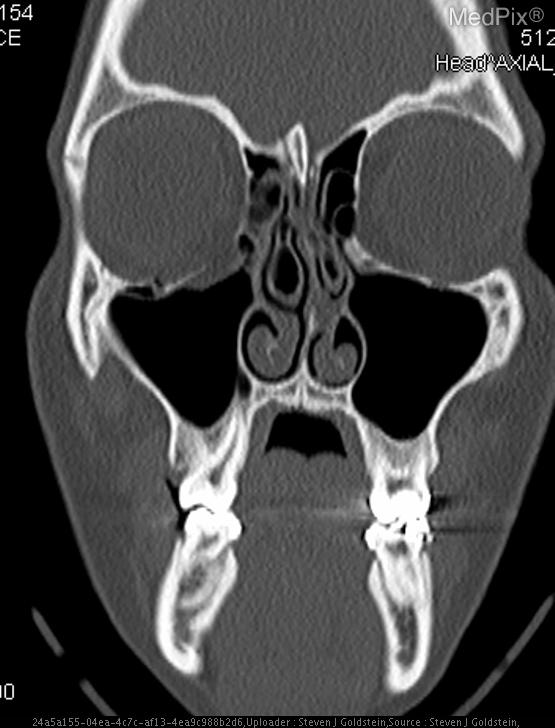

- Coronal CT image shows discontinuity of the orbital floor on the image-left (patient-right) side.

- Herniation of orbital fat and partial inferior displacement of soft tissue into the maxillary sinus on the image-left (patient-right).

- Air-fluid level within the right maxillary sinus (image-left side), consistent with hemorrhage or fluid collection.

- Intact orbital floor on the image-right (patient-left) side.

- Globes are intact bilaterally, without evidence of rupture or significant intraorbital hematoma.

- Nasal septum roughly midline; ethmoid air cells and remaining paranasal sinuses are clear.

Orbital floor (blowout) fracture on the image-left (patient-right) side. The CT demonstrates a defect in the orbital floor with herniation of orbital contents into the maxillary sinus, a classic feature of a blowout fracture. The presence of sinus fluid and continuity of orbital fat confirms disruption of the orbital floor. Context consistency: Consistent. Context title and imaging findings are in agreement for an orbital floor fracture. Confidence: 95%.